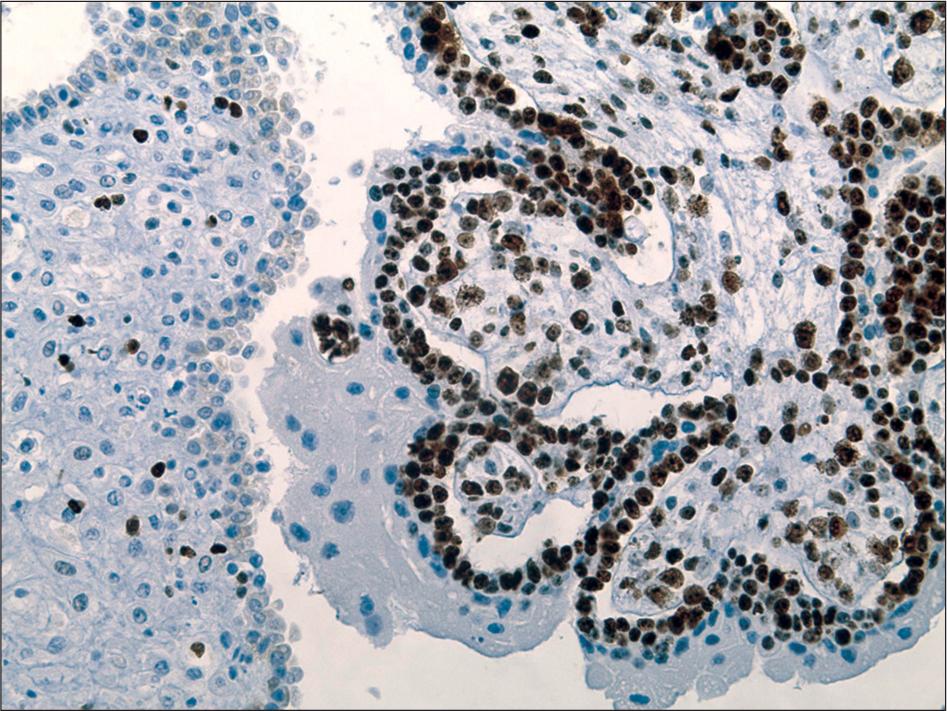

Immunohistochemical characteristics of complete moles_

| Positive Cells (%) | Ki-67 | p63 | p57 |

|---|---|---|---|

| n (%) | n (%) | n (%) | |

| 0 | 0 (0.0) | 0 (0.0) | 8 (100) |

| 10 | 0 (0.0) | 0 (0.0) | 0 (0.0) |

| 20 | 0 (0.0) | 0 (0.0) | 0 (0.0) |

| 30 | 0 (0.0) | 0 (0.0) | 0 (0.0) |

| 40 | 0 (0.0) | 0 (0.0) | 0 (0.0) |

| 50 | 0 (0.0) | 0 (0.0) | 0 (0.0) |

| 60 | 0 (0.0) | 3 (37.5) | 0 (0.0) |

| 70 | 4 (50.0) | 2 (25.0) | 0 (0.0) |

| 80 | 3 (37.5) | 3 (37.5) | 0 (0.0) |

| 90 | 1 (12.5) | 0(0.0) | 0 (0.0) |

| 100 | 0 (0.0) | 0(0.0) | 0 (0.0) |